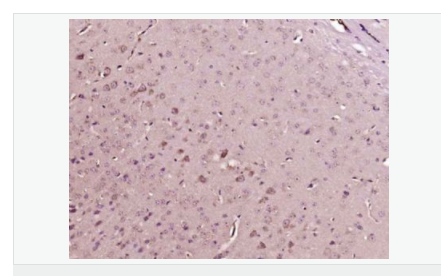

交叉反應:Human,Mouse,Rat(predicted:Phosphotyrosine) 推薦應用:IHC-P,IHC-F,ICC,IF

| 產品應用 | IHC-P=1:100-500 IHC-F=1:100-500 ICC=1:100-500 IF=1:100-500 (石蠟切片需做抗原修復) not yet tested in other applications. optimal dilutions/concentrations should be determined by the end user. |